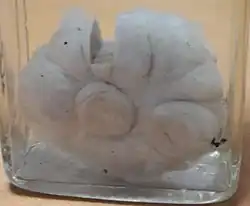

Macroscopic

Approximately 90% of fibroadenomas are less than 3 cm in diameter. However, these tumors have the potential to grow reaching a remarkable size, particularly in young individuals. The tumor is round or ovoid, elastic, and nodular, and has a smooth surface. The cut surface usually appears homogenous and firm, and is grey-white or tan in colour. The pericanalicular type (hard) has a whorly appearance with a complete capsule, while the intracanalicular type (soft) has an incomplete capsule.[9]